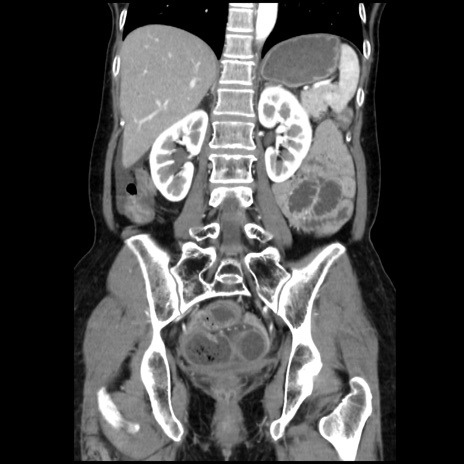

症例32(冠状断像)

【症例】40歳代 女性

【主訴】上腹部痛、嘔気・嘔吐

【現病歴】約9時間前頃から急に上腹部痛、嘔気、嘔吐が出現。改善しないため救急要請。

【既往歴】子宮頚癌(広汎子宮全摘術、放射線療法)、腸閉塞

【身体所見】腹部:平坦、軟、腸雑音亢進、上腹部を中心に腹部全体に圧痛あり。

【データ】WBC 8400、CRP 0.03